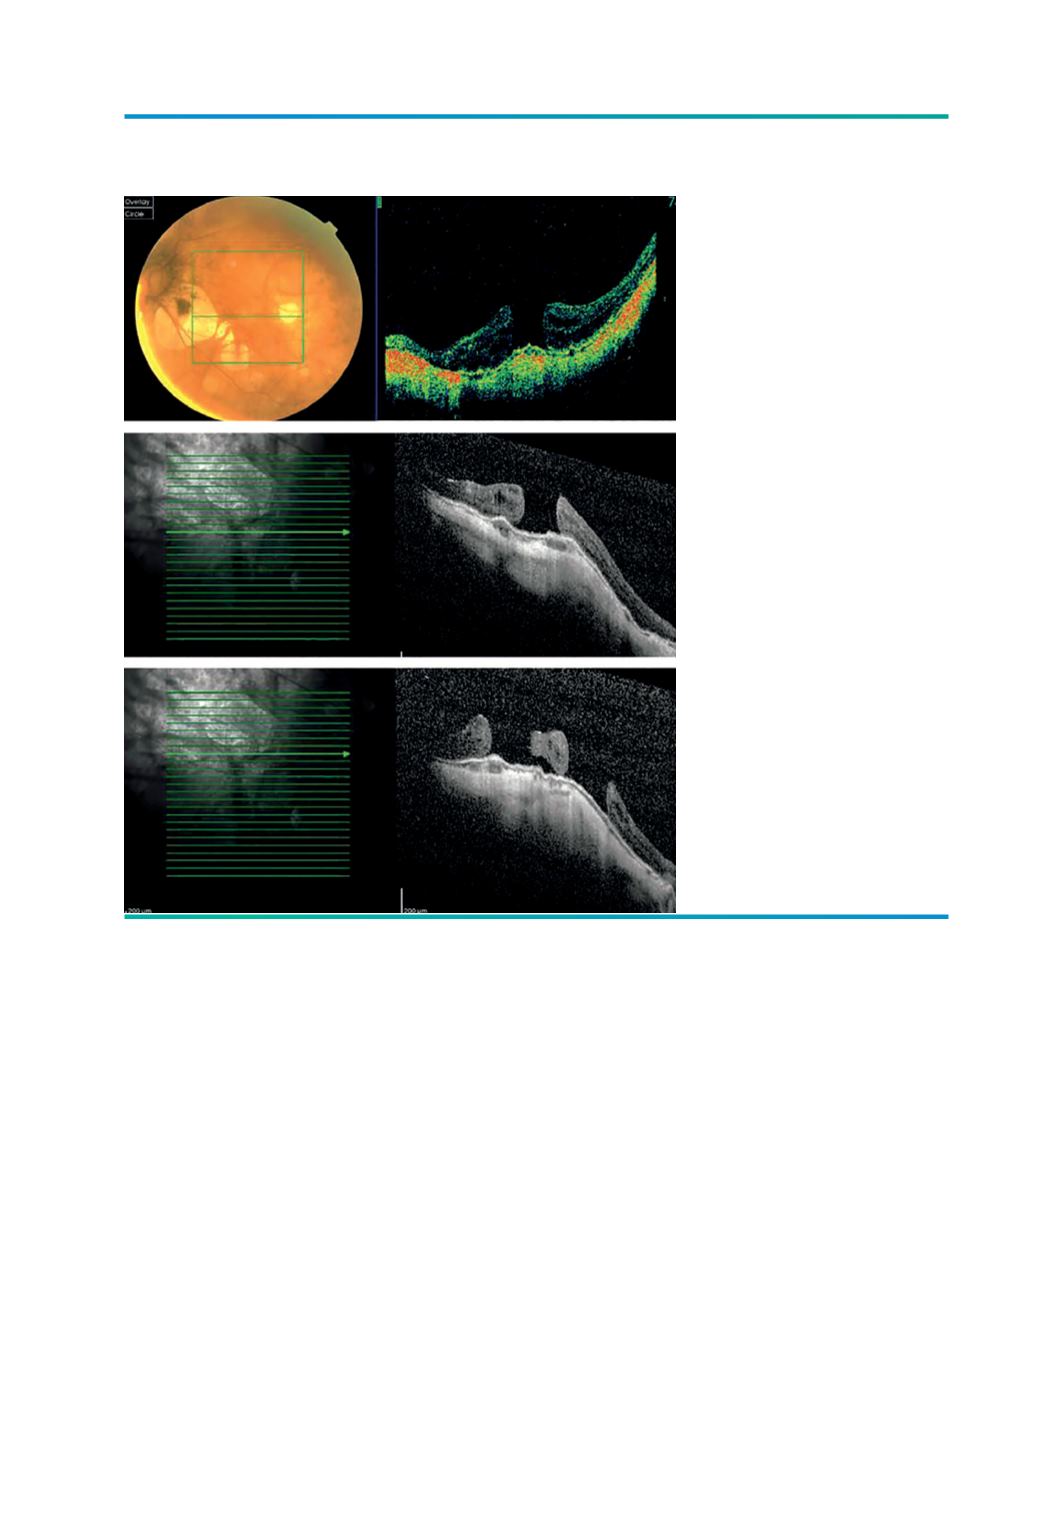

Figura 9.

A e B) Buraco macular

associado a alta miopia;

C) Duplo buraco.